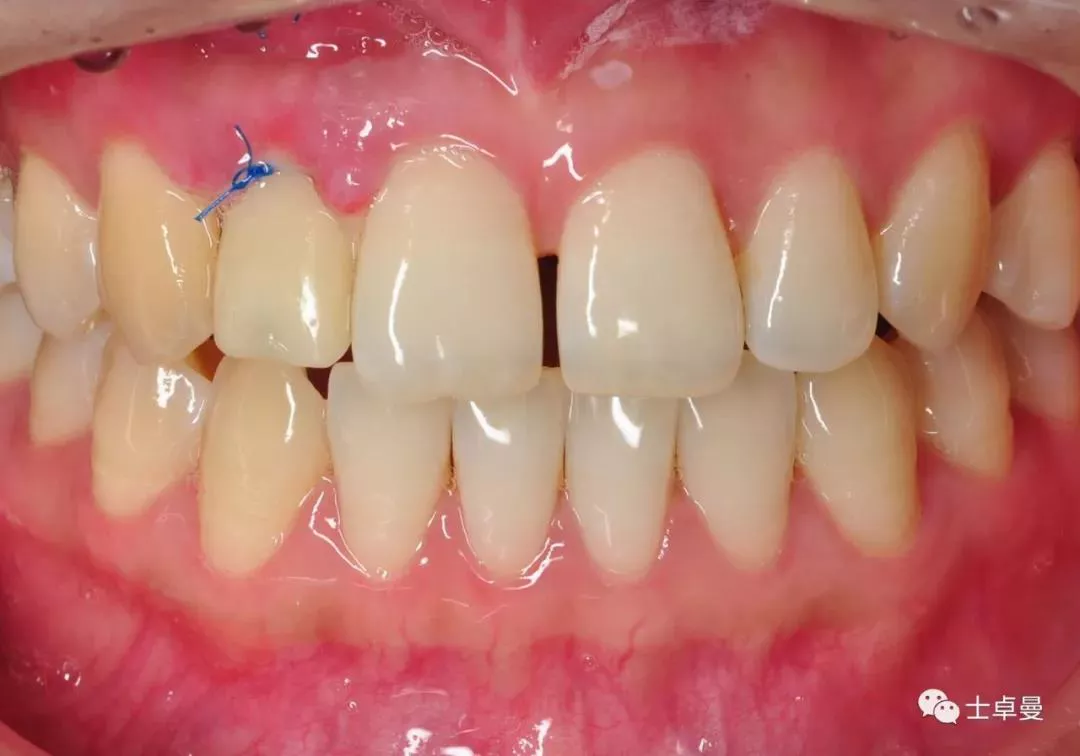

临时义齿口内就位

·       10天后拆线,临时义齿稳定,牙龈愈合良好;

拆线时愈合情况

龈缘曲线高度协调一致

口内完成修复当日